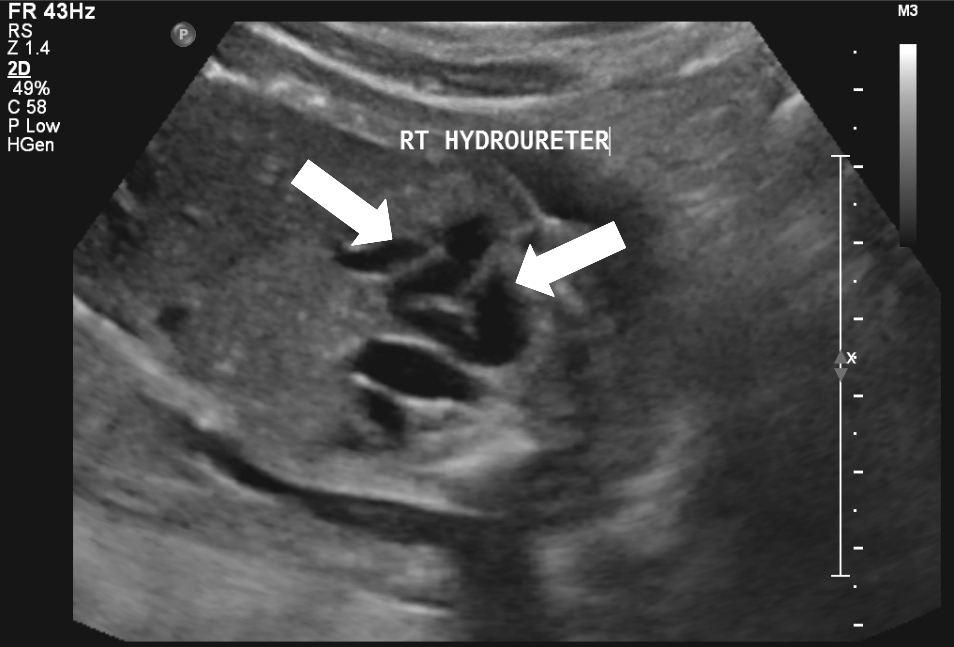

20 weken echografie: links: dikwandige blaas met verwijding van de plasbuis tot aan de kleppen (pijl): het “sleutelgat teken”. Onder: verwijde urineleiders. Bij kinderen gaan de urineleiders bij verwijding ook erg gekronkeld verlopen.

Normale plasbuis voorbij de kleppen

Plaats van de urethrakleppen

Verwijd eerste deel van de plasbuis tot aan de kleppen

Kleine, kramperige blaas met kartelige contour veroorzaakt door uitstulpingen van de blaaswand (divertikels)

Terugstroom van urine tot in de nier (vesico-ureterale reflux) en verwijde urineleider

Plasfoto met contrastmiddel (mictie cystogram)